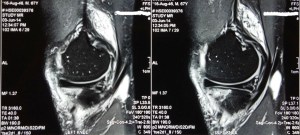

An MRI scan of his left knee showed a root tear of the posterior horn of his medial meniscus with loss of hoop stress, extrusion of the medial meniscus together with subchondral oedema of the medial tibial-femoral compartment and thinning of the cartilage of the medial compartment of his left knee.

In addition, the osteoarthritis of the kneecap compartment was also seen.

The MRI also confirmed that the lateral knee compartment was healthy and that the central cruciate ligaments were intact.